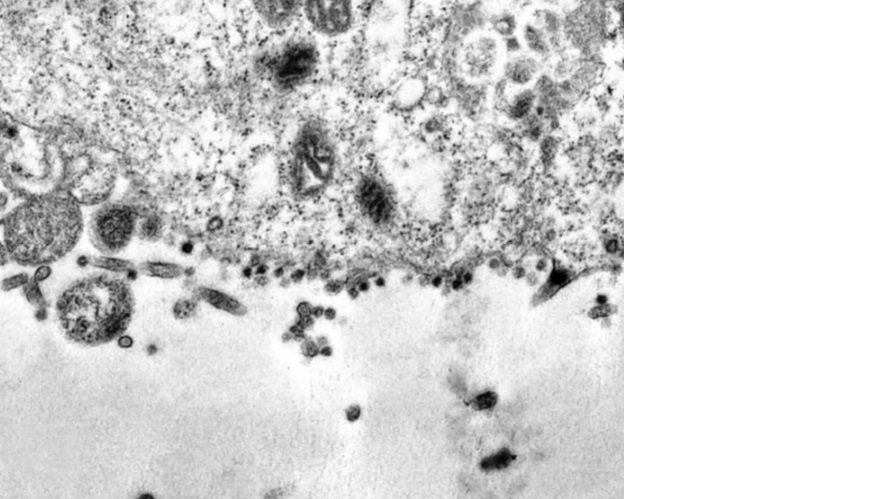

Bilim adamları tarafından elektron mikroskobuyla gerçekleştirilen bir çalışmada korona virüsün hücreyi enfekte etmeye çalıştığı an görüntülendi.

Korona virüsün insan hücrelerindeki yayılışı bilim adamları tarafından elektron mikroskobuyla kaydedildi.

Brezilyalı bilim insanları tarafından yapılan çalışmada koronavirüsün insan hücrelerinde oluşturduğu tahribat tüm yönleriyle açığa çıkarıldı.

Elde edilen görüntüde, kovid-19 virüsünün parçacıkları olan siyah noktalar, genetikten sorumlu olan bir sitoplazmayı enfekte etmeye çalışıyor.

'Korona' Latince taç veya hale anlamına gelmekte ve virüs partiküllerine adını veren dış kenarındaki sivri uçları açıkça görülüyor.